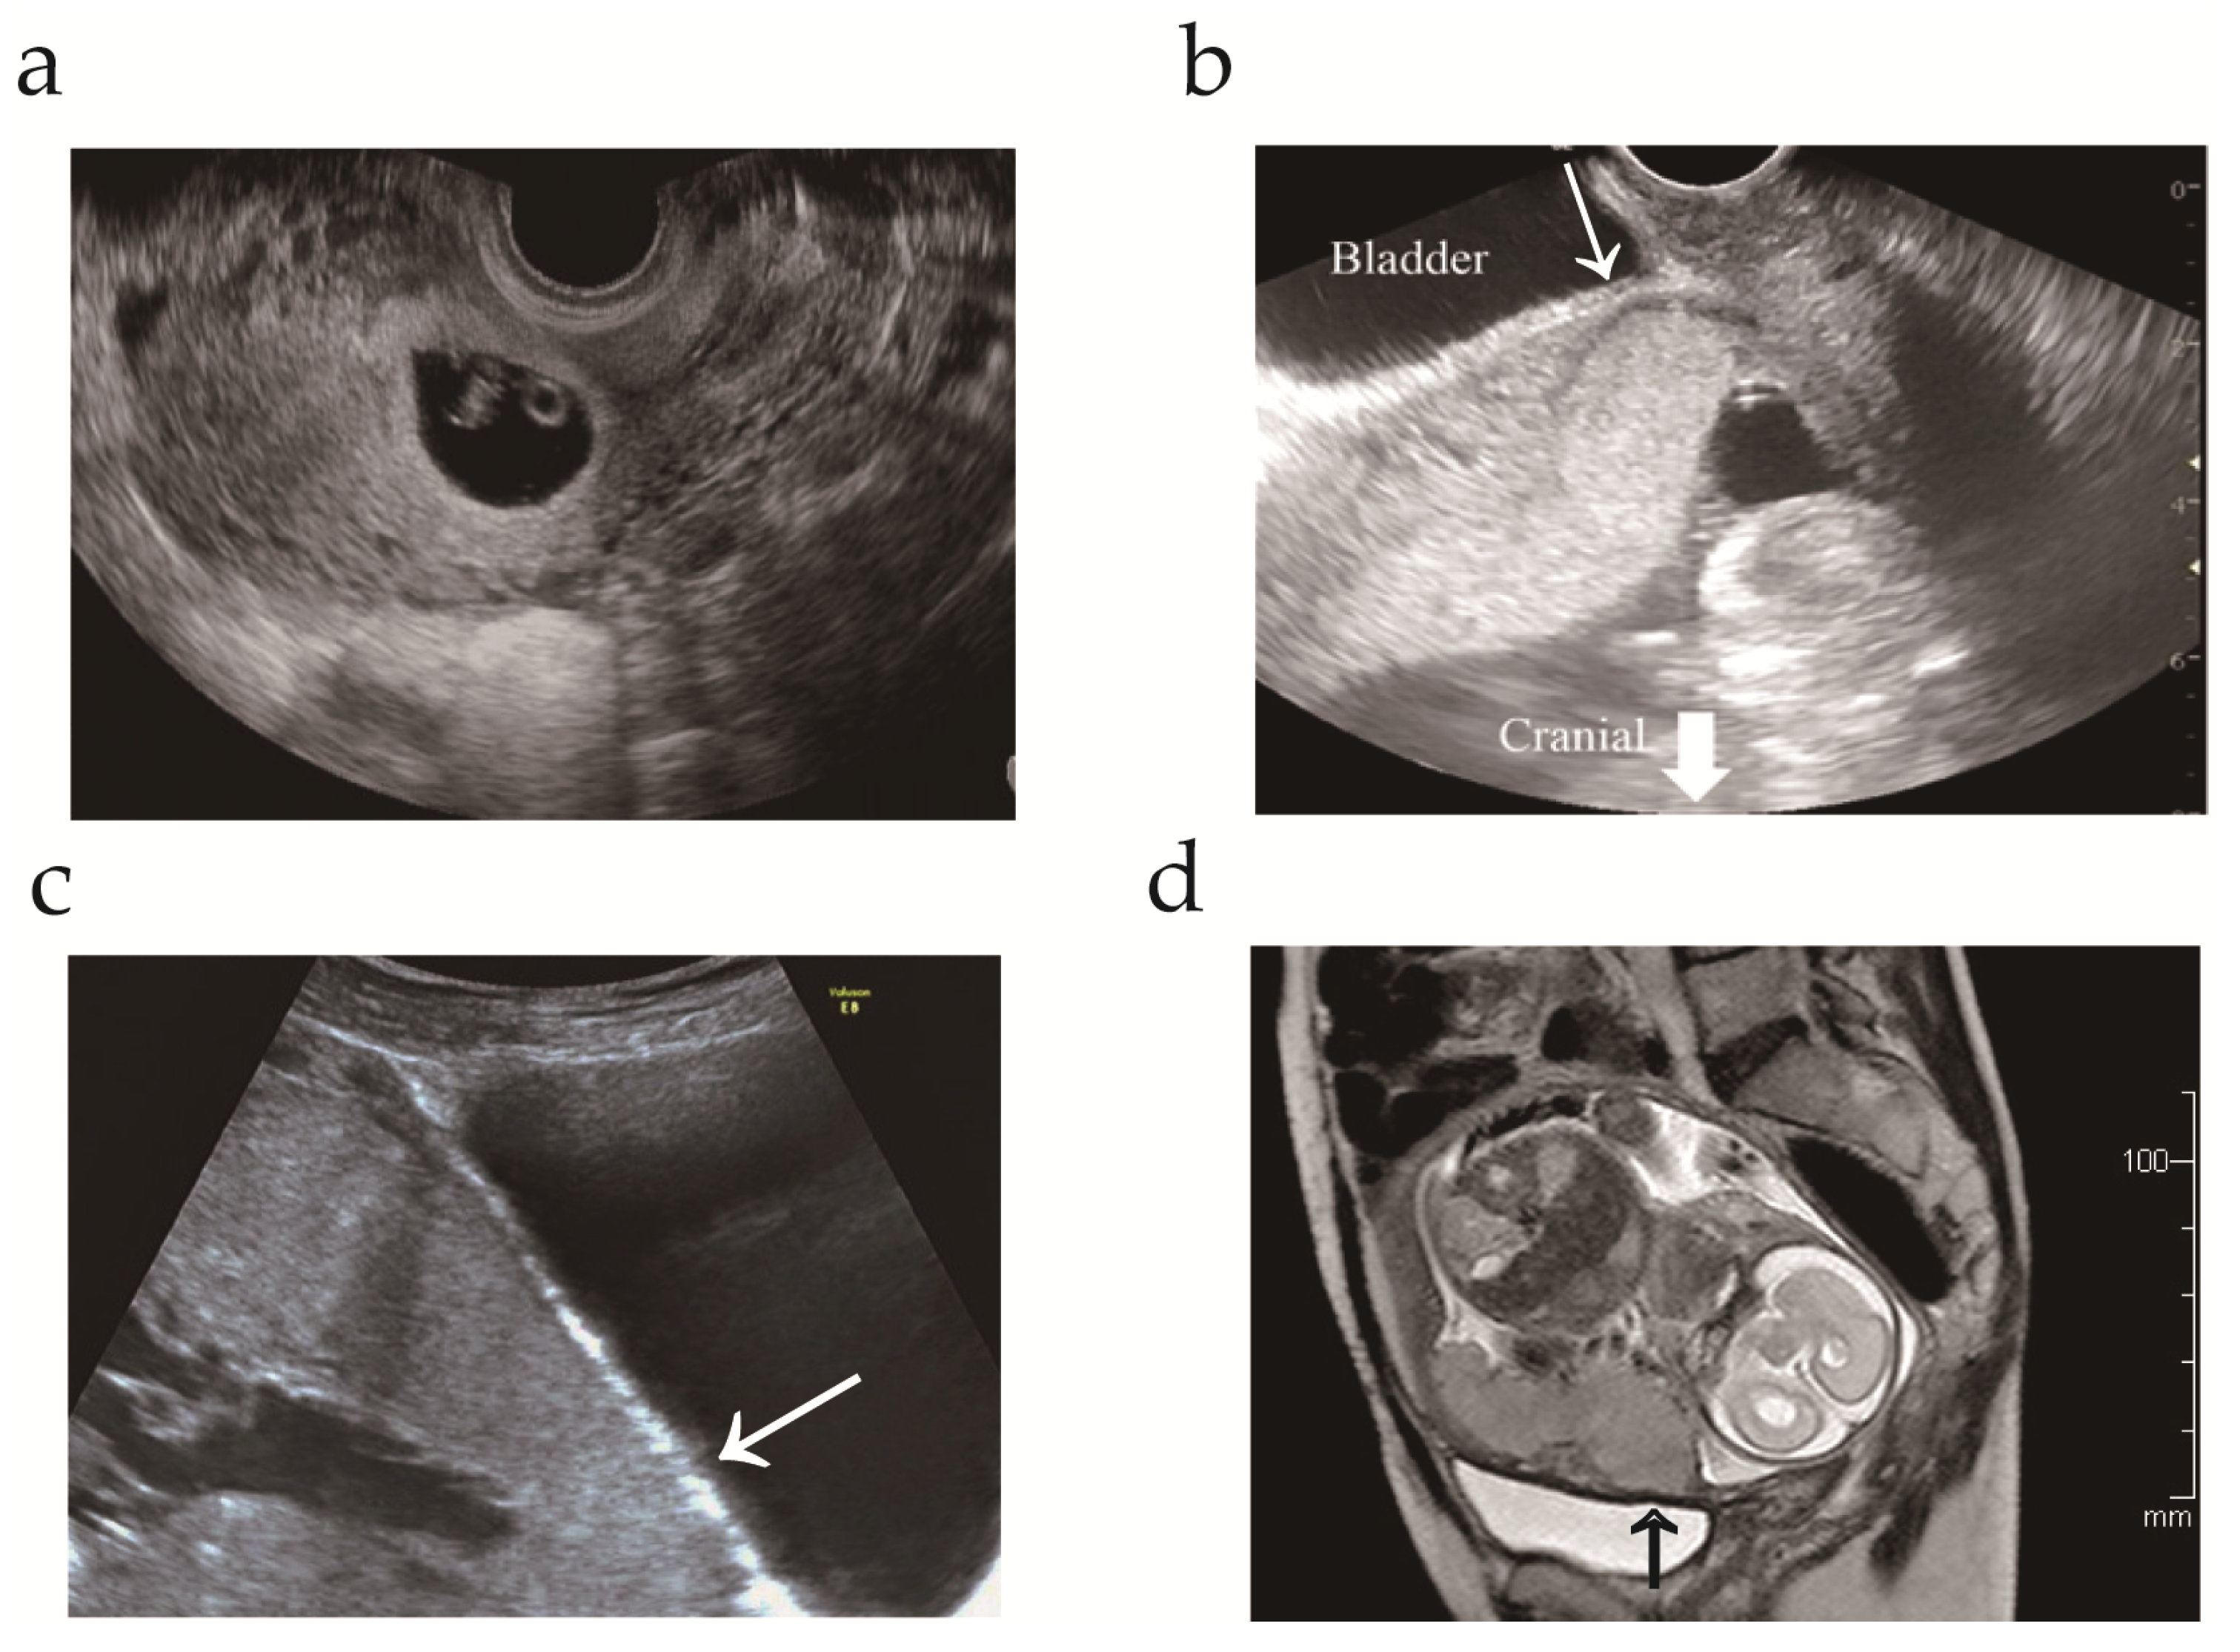

A 34-year-old, gravida 5, para 2, woman was referred to our hospital at 13 weeks’ gestation for high-risk pregnancy management. The patient had a history of appendectomy, right ovarian cystectomy, and cervical conization. The patient’s obstetric history was as follows: first pregnancy, term vaginal delivery; second pregnancy, lower transverse cesarean section at 36 weeks’ gestation; third pregnancy, spontaneous uterine rupture of a previous transverse scar at 15 weeks’ gestation (detailed information has been previously reported) [31]. Two-and-a-half years after the third pregnancy, the patient visited the community hospital with regard to a fourth pregnancy. Transvaginal ultrasonography at 8 weeks’ gestation revealed a gestational sac in the lower uterine segment (Figure 1a). Therefore, the patient was referred to our hospital due to the risk of uterine rupture.

At the patient’s first visit in gestational week 13, transvaginal ultrasonography revealed a single viable intrauterine fetus with appropriate growth and restricted space between the placenta and bladder (Figure 1b). To evaluate the cause of prior uterine rupture in the mid-trimester, trauma or congenital/acquired weakness of the myometrium was evaluated as follows: (i) ruling out uterine anomaly; (ii) exclusion of congenital disorders, such as Ehlers–Danlos type IV; (iii) confirmation that the previous uterine scar was a lower uterine incision for cesarean delivery; and (iv) confirmation of no trauma before uterine rupture. While placenta previa was excluded by transvaginal ultrasonography, magnetic resonance imaging and transabdominal ultrasonography indicated placenta increta without uterine dehiscence (Figure 1c,d). The patient was informed of the risk of maternal morbidity, specifically PAS, and chose to undergo cesarean hysterectomy without an attempt to remove the placenta at 34 weeks of gestation. The patient was well-educated regarding the symptoms that provide an early indication of uterine rupture.

Figure 1. Transvaginal and magnetic resonance imaging during pregnancy. (a) Transvaginal ultrasonogram at 8 weeks’ gestation revealing a gestational sac located in the lower uterine segment; (b) Transvaginal ultrasonogram at 13 weeks’ gestation revealing decreased space (arrow) between the placenta and bladder; (c) Transabdominal ultrasonogram at 33 weeks’ gestation. The arrow indicates the loss of the normal hypoechoic retroplacental zone; (d) T2 magnetic resonance image at 25 weeks’ gestation. The arrow indicates the loss of the thin, dark subplacental myometrium zone.